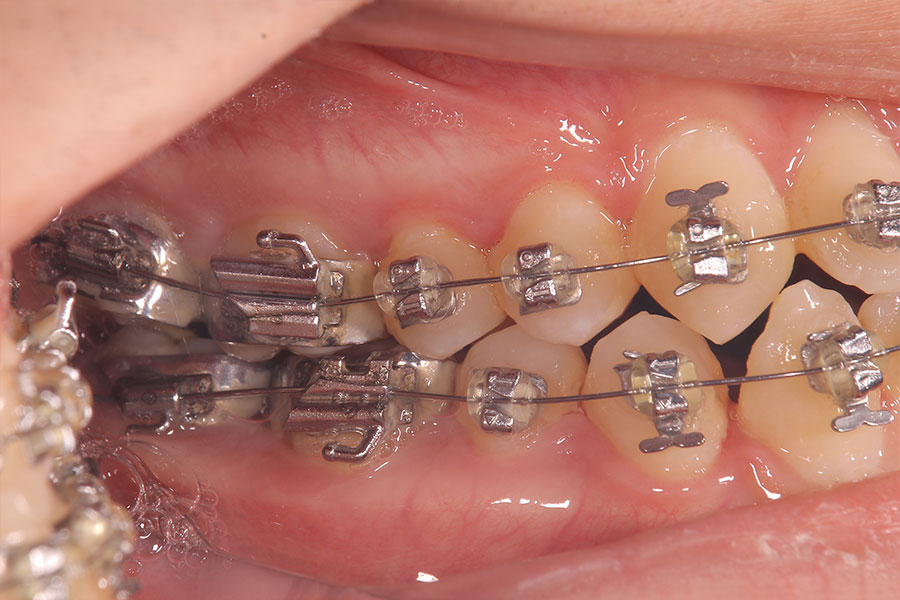

Before -正面-

After -正面-

Before -側面-

After -側面-

| 施術内容 | ワイヤー矯正から、目立ちにくくメタルフリーなインビザラインへ変更しました。 金属アレルギーの不安が軽くなり、取り外しできることで清掃性も向上。見た目も自然で、治療中のストレスが少ない矯正方法です。 |

|---|---|

| 治療期間 | 2年間 |

| 費用 | インビザラインフル 767,800円 リテーナー 30,000円 |

| リスク・副作用 | 治療にともない、歯の破折や歯質の削合、場合によっては抜歯が必要となることがあります。また、金属や補綴物を除去する際に、完全に除去できない場合もあります。 |